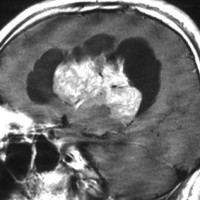

無症状の若い女性に偶然発見された例

central neurocytomaは腫瘍実質部分が多いものです。しかし,この例のように腫瘍の大部分をのう胞が占める症例もあります。

anterior transcallosal apprroachで亜全摘出しました。20代の女性でしたが,その後,子どもも生まれて元気です。

腫瘍の位置から,透明中核が発生母地であることが推測されます。central neurocytomaは,惻脳室壁にべとべとくっつくので,脳質上衣からの剥離は簡単ではありません。鑑別しなければならないのが,成人の毛様細胞性星細胞腫ですが,この症例では決定的な鑑別点はないでしょう。のう胞性の毛様細胞性星細胞腫と同様に,腫瘍の増殖力は低く無理して全摘出するものではありません。